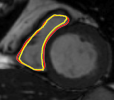

Figures 8 and 9 shows some sample tracking results of the proposed method and Medviso on full cardiac cycles of two different cases on both the LV dataset and the RV dataset. The ground truth (yellow) is superimposed when available. A summary of the results on the entire datasets is shown in Table I. The accuracy with respect to ground truth is measured using average perpendicular distance (APD) and dice metric (DM) for left ventricle, and Hausdorff distance (HD) and DM for the right ventricle. These metrics are chosen since they are the standard ones used on these datasets. Both qualitative and quantitative results show that our proposed method leads to more accurate segmentation of the ventricles and thus leads to less interaction than segmentation propagation schemes in than Medviso.

| initial | ventricle tracked (red - algorithm result, yellow - ground truth) | |||

|---|---|---|---|---|

|

Medviso |

||||

our method |